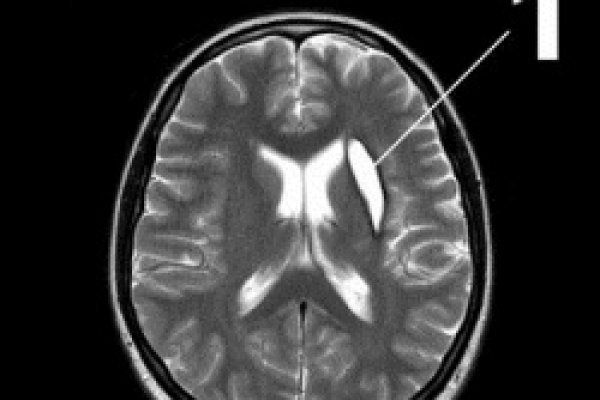

Что же такое «киста головы»? Это образование, которое содержит в себе жидкость, располагающаяся в капсуле в форме пузыря. Анатомически, между височной и теменной долей существует полость, заполненная жидкостью. Когда по каким-либо причинам, которые мы рассмотрим далее, образуются отмершие ткани, жидкость с этой части пытается занять место отмерших тканей, из-за чего образуется капсула, которая и образует кисту. Чаще всего киста появляется в так называемом паутинообразном покрытии коры полушарий мозга. Это связано с тем, что данная часть мозга легко подвергается ушибам, травмам и воспалительным процессам, сопутствующим им. По статистике чаще болеют дети, подростки и мужчины, нежели женщины.

- Арахноидальная. Образуется на оболочке мозга. Чаще всего сдавливает участки мозга, о чем свидетельствуют частые судороги и расстройства неврологического характера больного.